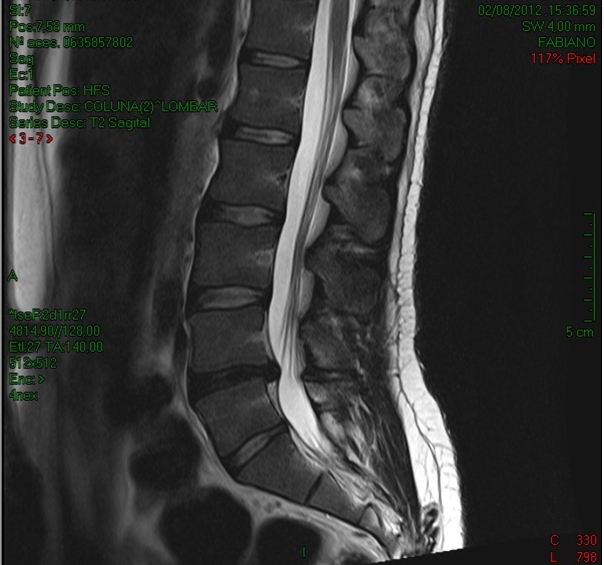

Será que realizar um exame de imagem (ex: Ressonância Magnética, Tomografia) quando alguém tem dor lombar é realmente importante?

Uma vez que, através do exame clínico tenham sido descartadas condições de ameaça à vida ou doenças sistêmicas (como câncer, doenças em órgãos internos e outras) a utilização da imagem não parece necessária.

MODIC et al (2005) e ASH ET al (2008) observaram, em indivíduos com dor lombar aguda ou radiculopatia, que o conhecimento dos resultados da Ressonância não altera o resultado do tratamento conservador e faz com que os indivíduos tenham uma sensação de bem estar inferior.

CHOU ET al (2009) numa revisão sistemática, concluem que a realização de exames de imagem para dores lombares em pessoas sem condições graves não interfere com a melhoria dos sintomas, e que nesses indivíduos deve-se evitar sua requisição rotineira ou imediata nas situações de dor aguda ou subaguda.

ANDERSEN (2011) realizaram uma revisão da literatura sobre a relação entre exames de imagem e o tratamento subseqüente, concluindo que além de não promover melhorias no tratamento subsequente, a não realização do exame de imagem não prejudica a identificação de condições ou patologias mais sérias além de proteger o paciente contra a radiação (radiografias ou tomografias computadorizadas) e trazer economia de custos.